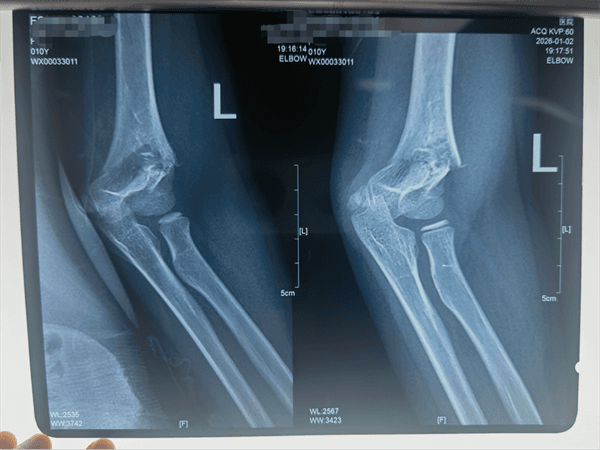

时间就是生机,莹莹从受伤到抵达医院不到2小时,这一“黄金救治窗口”为后续治疗奠定了良好基础。小儿外科接诊后,立即开展细致检查,发现莹莹左肘肿胀明显,呈半屈曲保护姿态,可触及骨摩擦感,肘后三角关系改变,均为肱骨髁上骨折典型体征。幸运的是,莹莹左手“OK”征阴性、虎口区无麻木、桡动脉搏动有力,提示重要神经血管未受损伤,为治疗赢得关键契机,X线片也证实为“左肱骨髁上骨折”。

肱骨髁上骨折是儿童最常见的肘部骨折之一,手术治疗须兼顾骨折复位精度与骨骺(生长板)保护,直接关乎莹莹未来骨骼发育。莹莹的微创精准手术在全身麻醉下开展,手术团队在C臂透视机精准引导下,进行“毫米级”精细操作:无需大开刀口,仅通过皮肤外对抗牵引和手法复位,便将移位骨折端完美对合;随后将细如发丝的克氏针经皮穿入交叉固定骨折块,全程出血极少,并通过关节造影确认关节面平整。该微创术式最大程度降低了对周围软组织及骨骺的损伤,为莹莹远期功能完全恢复提供有力保障。

术后,莹莹返回小儿外科病房,在医护团队的精心照料下恢复迅速。术后三天复查X线显示,内固定位置完美,骨折对位线满意。1月7日,莹莹康复出院。出院时,医护人员详细告知家长家庭护理要点及功能锻炼方法,为莹莹后续恢复保驾护航。